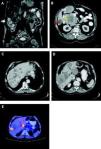

In 4 patients (33%) the liver metastases occurred synchronously with the primary tumor and in 8 cases (77%) metachronously, with a median time interval of 41 months (range, 23-76). The liver metastases were verified by MRI, CT or PET-CT (Figure 1). In four cases with unclear radiological findings, histopathological examination after CT guided needle biopsy was performed. In immunohis-tochemical analysis, all metastases presented typical morphology for GIST metastasis and KIT positivity. The clinical characteristics of primary tumors and of liver metastases are listed in table 1.

A. MR-enteroclysis: solitary liver metastasis (segment 6). B. Abdominal CT: GIST of the duodenum (yellow arrow) with synchronous liver metastasis (segment 4; white arrow) and cystic lesion (segment 6; red arrow). C and D. Abdominal CT: multiple hepatic metastatic disease of GIST. E. Abdominal PET-CT: bilobar liver metastase (segment 6 with contact with diaphragm, Standard Uptake Values-SUV max 6.7 and segment 2/3, SUV max. 7.6).